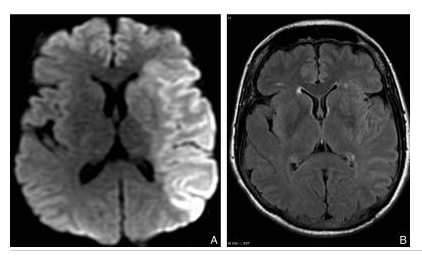

Signes d’AVC ischémique en phase aiguë au scanner.

Examen sans injection de produit de contraste iodé réalisé à 6 heures de l’installation du déficit. Les coupes axiales réalisées au niveau temporal (A) et insulaire (B) montrent une hypodensité homogène touchant la substance grise et la substance blanche, à contours bien limités, discrètement expansive avec effacement des sillons corticaux, dessinant le territoire de l’artère cérébrale moyenne droite. Hyperdensité spontanée de l’ACM thrombosée (flèches).